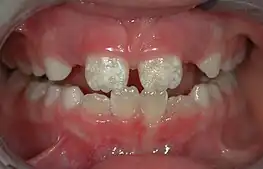

Some groups have spoken out against fluoridated drinking water, for reasons such as the neurotoxicity of fluoride or the damage fluoride can do as fluorosis. Fluorosis is a condition resulting from the overexposure to fluoride, especially between the ages of 6 months and 5 years, and appears as mottled enamel.[3] Consequently, the teeth look unsightly, although the incidence of dental decay in those teeth is very small. Where fluoride is found naturally in high concentrations, filters are often used to decrease the amount of fluoride in water. For this reason, codes have been developed by dental professionals to limit the amount of fluoride a person should take.[35] These codes are supported by the American Dental Association and the American Academy of Pediatric Dentistry.

Fluorosis leads to mottled enamel and occurs from overexposure to fluoride.[25]